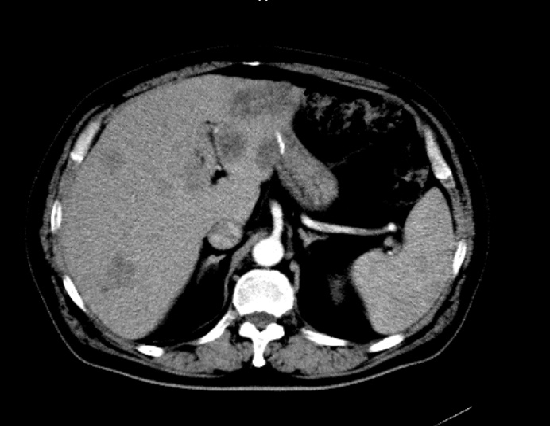

2020-05:

2020-05:

胸腹盆增强CT(2020-05-08):直肠癌治疗术后,左下腹造瘘术后,肝脏多发转移较前增多增大,双肺气肿,主动脉及冠状动脉硬化,双肾囊肿

诊断:直肠腺癌术后,转移(肝)。